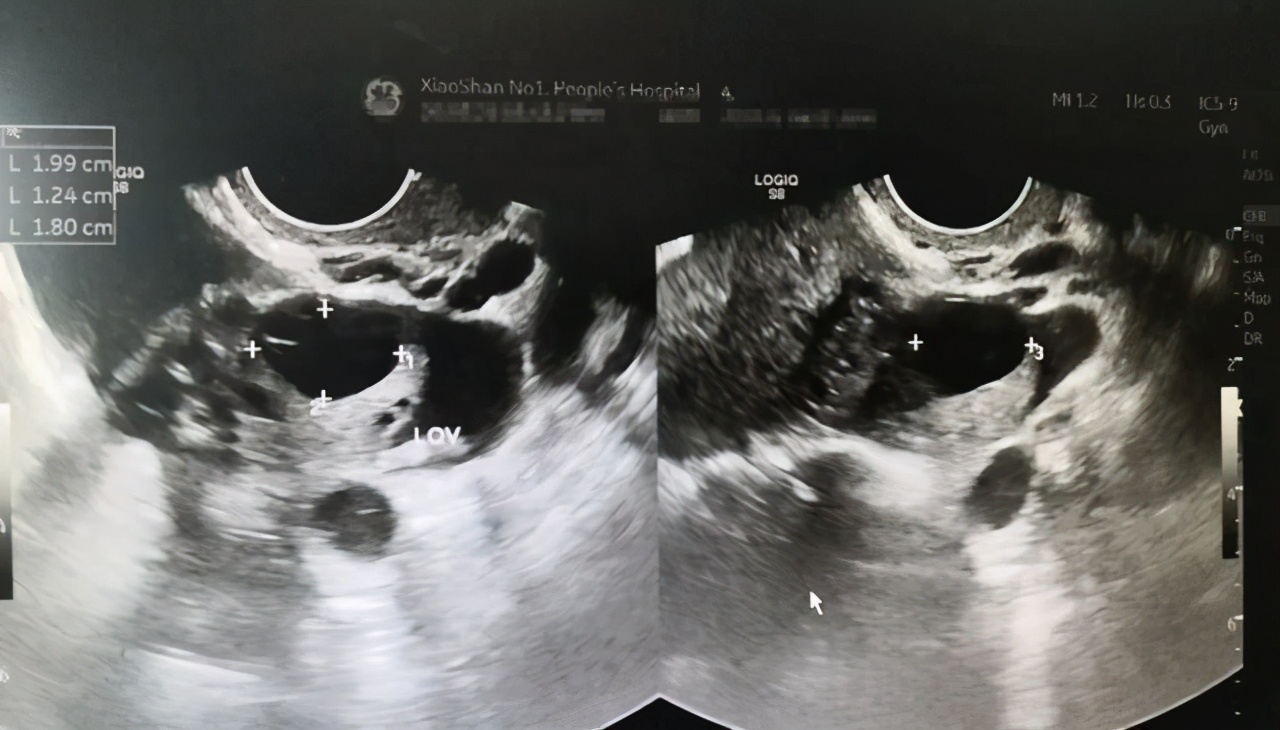

医生皱着眉头,开始给女孩做检查,经过腹腔B超检查发现,女孩左侧卵巢已经异常变大,里面的黄体出现了血肿。经过初步判断,该女生肚子里的出血量已经达到了1500ml,医生诧异地问:你想要她命吗?到底在搞什么?